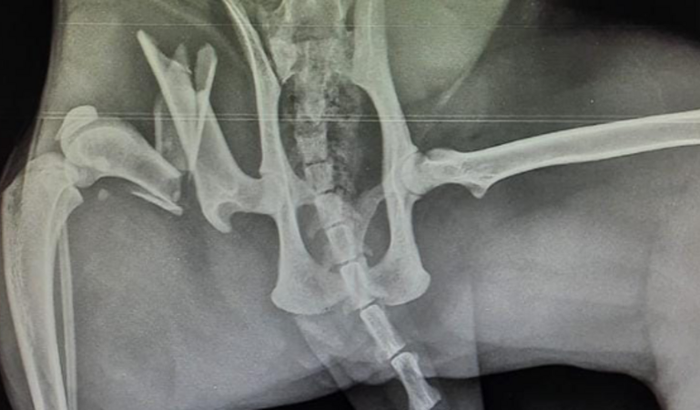

Na mesma noite, dia 19/05, a levei ao veterinário onde ela fez diversos exames e foram constatadas fraturas e luxações. Ela teve que tomar Morfina e desde então está internada.

A Bolinha provavelmente sofreu um trauma muito grande, pois teve o fêmur quebrado em 3 partes e precisa fazer uma cirurgia de urgência para poder voltar a andar.